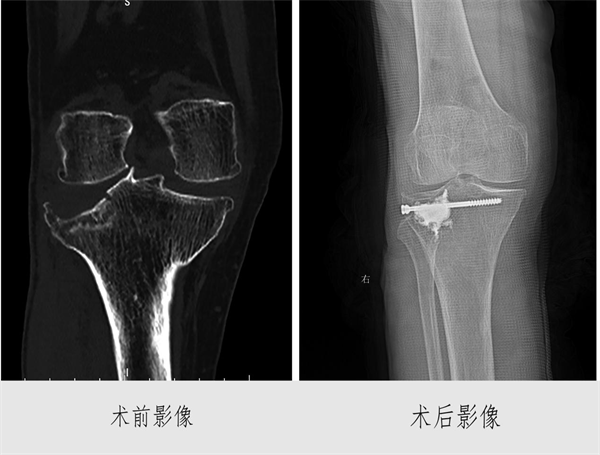

患者刘某为83岁女性,患严重骨折疏松症,因胫骨骨折住院,诊断为Schatzker 分型Ⅲ型骨折。外二科组织专家会诊,详细讨论治疗方案,考虑患者年龄较大,运用微创手术损伤小,出血少,容易恢复,通过缜密术前规划,为其制定了微创手术方案。3月27日该院医生使用C臂X光机和关节镜进行辅助操作,成功地将骨折复位并采用PKP技术进行内固定。手术过程十分顺利耗时仅1.5小时。术后对患者进行了密切观察和护理。术后患者及家属对手术效果非常满意。

据悉,省内外开展此类手术只有少量报道,在娄底市第二人民医院外二科属于首次开展。该科将C臂X光机、关节镜、PKP技术联合应用在一起开展微创手术是一次富有成效的技术创新尝试,体现了医务人员的专业钻研能力。